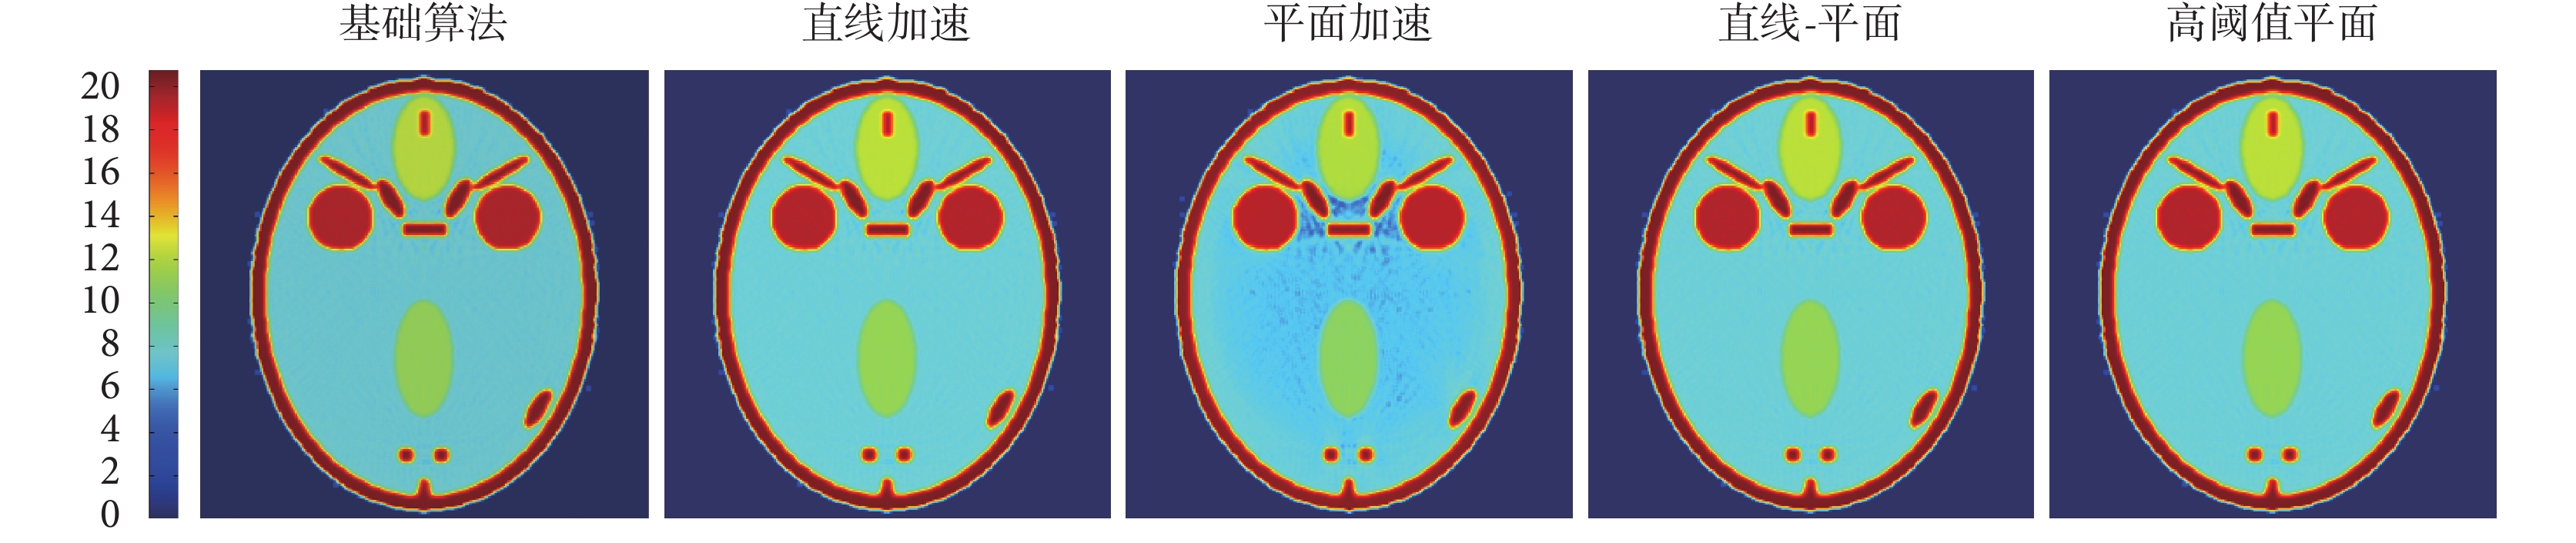

由式(3)和式(4)可以計算有效電子密度圖像和有效原子序數圖像,如圖 10 和圖 11 所示。

從圖 10 可以看出三種算法重建的電子密度圖像幾乎是一樣的。圖 11 中重建的三種算法有效原子序數圖像也相差不多,但平面加速算法的中部區域卻有一些差異。這是因為平面加速算法的設定閾值 th 過小,造成了計算誤差。因為計算原子序數的公式有分母項,造成了誤差放大。加大平面加速算法的設定閾值 th,可以解決這一問題,但會增加計算時間。直線-平面混合加速算法也可以解決這個問題,而且計算時間相對于高閾值平面加速算法會降低。為了驗證這一猜想,我們用高閾值平面加速算法和直線-平面混合加速算法進行了重建,并得到相應原子序數圖,如圖 11 所示。從圖 11 可見,直線-平面混合加速算法和高閾值平面加速算法重建的效果與基礎算法、直線加速算法的效果是一樣。